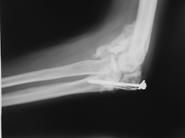

Fibröz displazinin altı aylık aralarla alınacak filmlerlekontrolu yapılır. Bifosfanatlar medikal tedavide altın standarttır. Patolojik kırık veya patolojik kırık gelişme ihtimali yüksek olduğunda kanal içi çivileme ile tedavi edilir. Deformite geliştiğinde düzeltici osteotomi ve internal osteosentez uygulanır. Cerrahi tedavide; küretaj +grefonaj, yüksek nüks nedeni ile gözardı edilir, kanal içi osteosentez uygulanır. Ayrıca deformitenin gelişmesini engellemek için de geniş lezyonlarda koruyucu internal fiksasyon da yapılır. Büyüme kıkırdaklarının aktif olduğu dönemlerde intramedüller çivileme bu bölgelere zarar verebilir. Tedavide amaç deformitelerin oluşmasını engellemek ve var olanı düzeltmektir. Monostotik formlarda %0,4 oranında kötü huylu tümöre (malignite) dönüş bildirilmiştir.